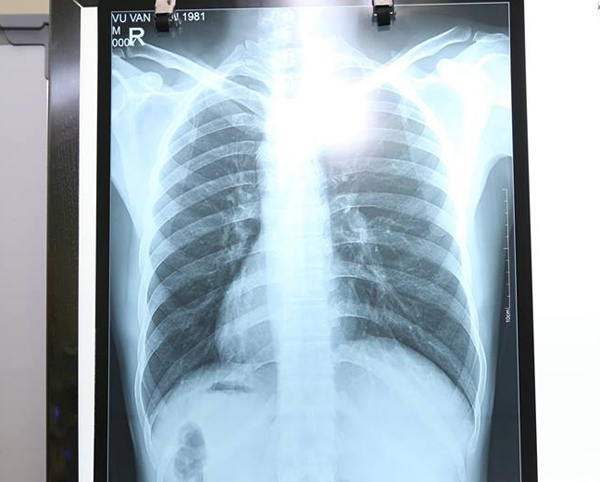

Kết quả chụp X-quang của bệnh nhân.

Tuy nhiên, điều khiến các bác sĩ kinh ngạc là tim cùng các phủ tạng khác trong lồng ngực và bụng của bệnh nhân đều ở vị trí ngược so với bình thường, tim và dạ dày đều ở bên phải còn gan, ruột thừa nằm ở bên trái.